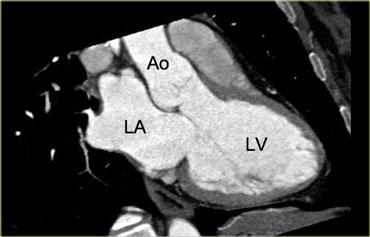

Mặt cắt 3 buồng

Khi xác định được ranh giới giữa van hai lá và van động mạch chủ trên các lát cắt ngang và xoay hình ảnh từ điểm này, có thể tái tạo mặt cắt 3 buồng như hình ảnh bên trái.

Trên hình ảnh này, nhĩ trái, thất trái, van hai lá, van động mạch chủ và đoạn gần của động mạch chủ lên đều được hiển thị.